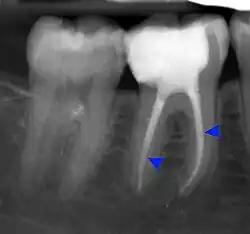

Apical abscess associated with roots of a lower molar.

Apical periodontitis is acute or chronic inflammation around the apex of a tooth caused by an immune response to bacteria within an infected pulp.[20] It does not occur because of pulp necrosis, meaning that a tooth that tests as if it's alive (vital) may cause apical periodontitis, and a pulp which has become non-vital due to a sterile, non-infectious processes (such as trauma) may not cause any apical periodontitis.[10]: 225  Bacterial cytotoxins reach the region around the roots of the tooth via the apical foramina and lateral canals, causing vasodilation, sensitization of nerves, osteolysis (bone resorption) and potentially abscess or cyst formation.[10]: 228

The periodontal ligament becomes inflamed and there may be pain when biting or tapping on the tooth. On an X-ray, bone resorption appears as a radiolucent area around the end of the root, although this does not manifest immediately.[10]: 228  Acute apical periodontitis is characterized by well-localized, spontaneous, persistent, moderate to severe pain.[6]: 125–135  The alveolar process may be tender to palpation over the roots. The tooth may be raised in the socket and feel more prominent than the adjacent teeth.[6]: 125–135